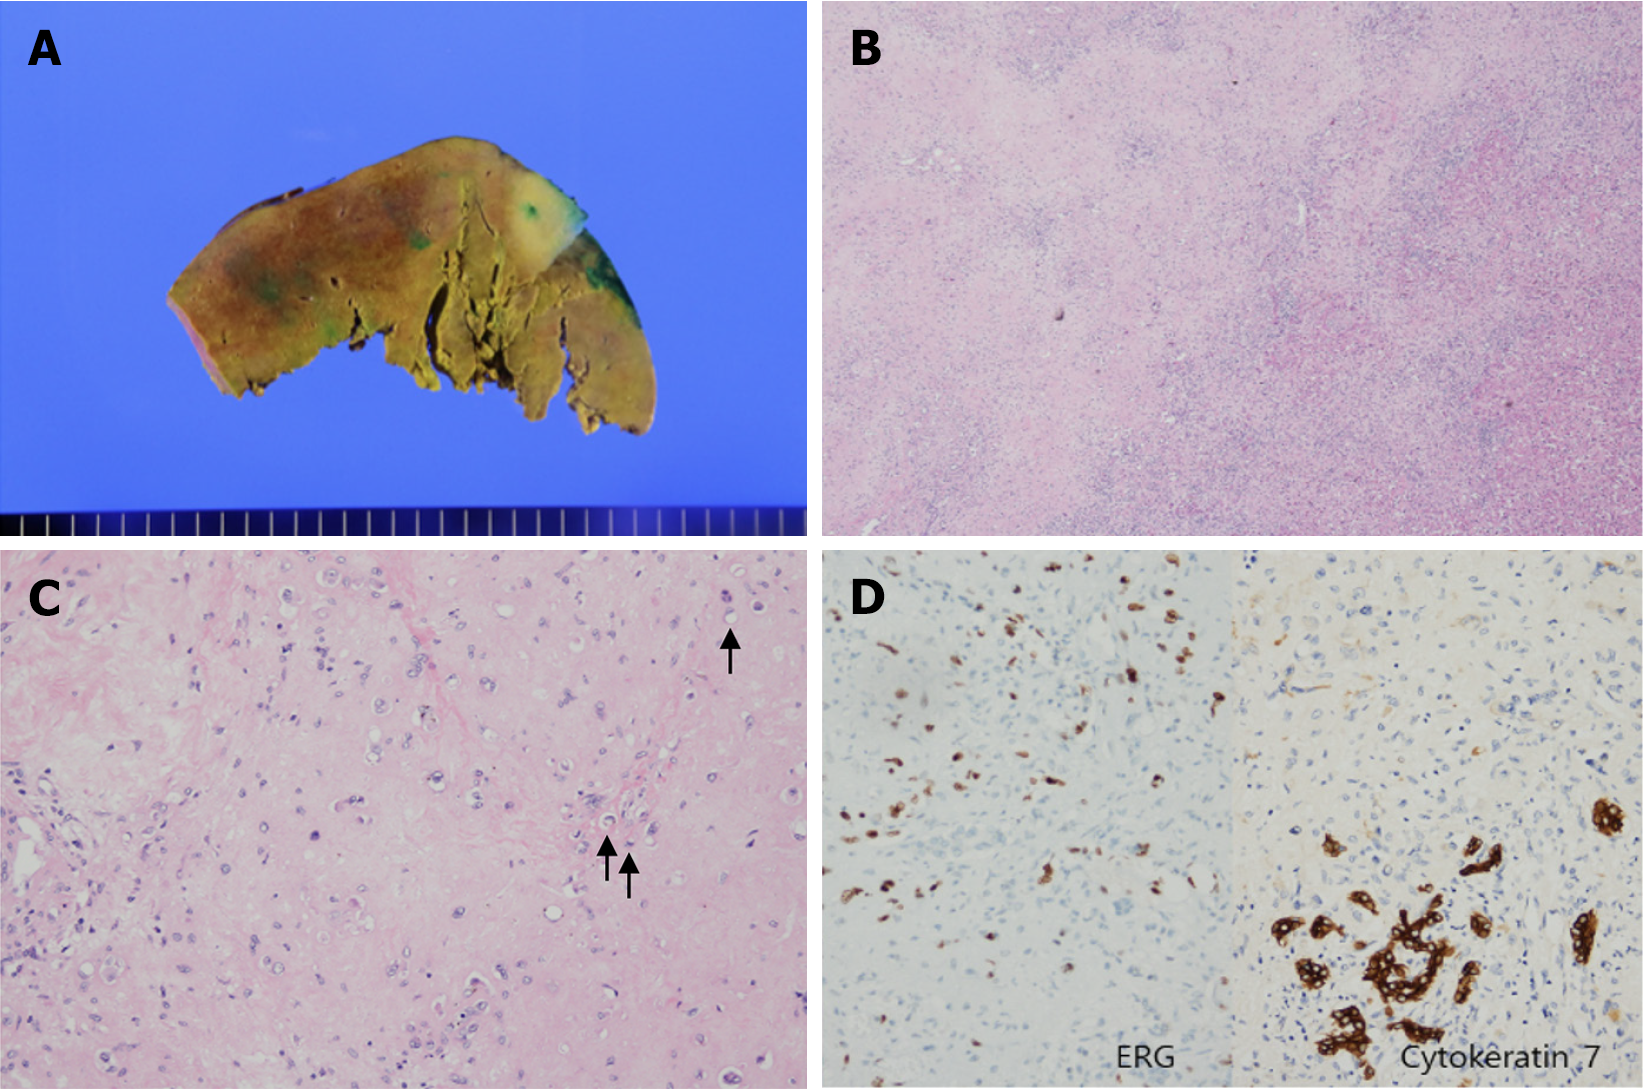

The initial preoperative diagnosis was either cholangiocarcinoma or recurrent RCC carcinoma. However, the posto

Although genetic analysis could not be performed due to insurance limitations, immunohistochemical staining of the tissue biopsy supported the diagnosis. The tumor tested positive for vascular endothelial markers (ERG, CD31, CD34, and FLI1), confirming its vascular origin. Additionally, CK7 positivity suggested a resemblance to the intrahepatic bile ducts. Focal positivity for TFE3 raised the possibility of YAP-TFE3 fusion. Based on these findings, a diagnosis of HEHE was considered appropriate.

The patient developed wound pain, along with mild pulmonary and peripheral edema, which was successfully managed with analgesics and diuretics. No significant complications were noted and the patient recovered well. Histopathological examination confirmed the diagnoses of HEHE and fatty liver disease. The patient was discharged in a stable condition on postoperative day 12.